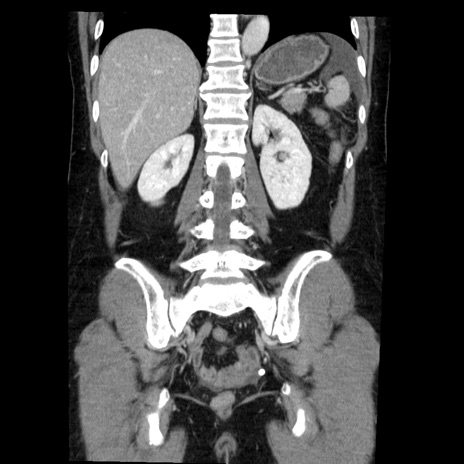

症例6(冠状断像)

【症例】50歳代女性

【主訴】下腹部痛

【現病歴】本日朝より下痢2回あり。 昼食を食べた後、嘔吐3回、下腹部痛認め、症状軽快せず、当院救急搬送。

最終食事:本日昼(生ものなし)。 昨日の夜、刺身を食ぺたとのこと。周囲に同様の症状の者なし。普段、排便は毎日あるとのこと。

【既往歴】卵巣癌術後(8年前に当院で卵巣摘出)

【身体所見】 意識清明、腹部:平坦、腸蠕動音→、やや硬、下腹部自発痛・圧痛あり、反跳痛あり、筋性防御なし。

【データ】WBC 16000、CRP 0.01